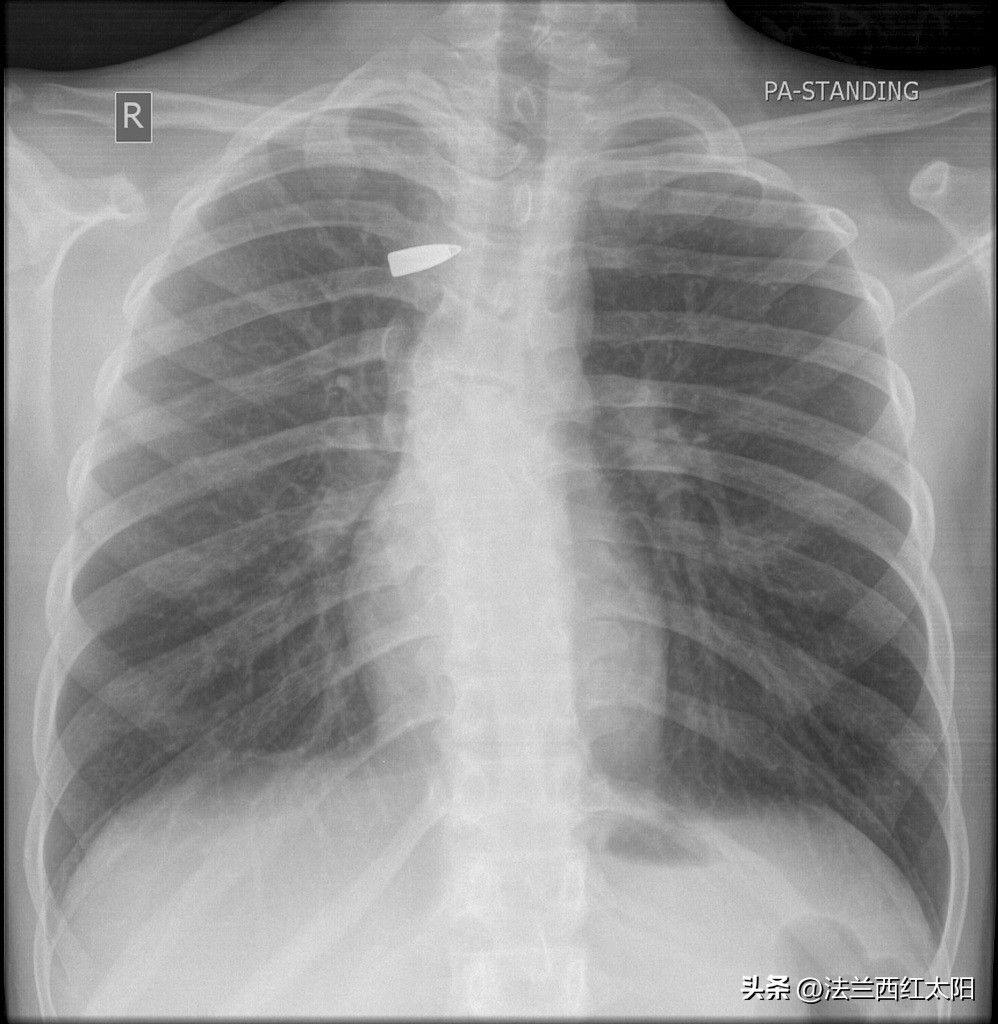

X光片中一颗弹头在肺里,就安静地呆在心脏的旁边

优秀的后方大医院里,伤员可以通过止血、缝合并使用抗生素,那么有可能会得到好的结果。但是,在战地临时医护区里,贸然(或不得已)打开伤口,会有更多的血液流出,更多的感染可能,情况也许会变得更加糟糕。这就是为什么在现实世界中,医生专注于止血(有时使用相当基本的手段),并将伤员尽量置于能够适当清洁、消毒和缝合的环境中。操作过程中如果弹头(或弹片)能轻松掉出则罢,否则会迅速将伤口缝合,之后身体会用结缔组织囊肿包围异物,使之不会或减轻造成二次伤害。以后的岁月里,除了偶尔在X光检查中能被看到外,弹头(或弹片)大多会安静地呆在原地,一般不会带来任何问题。